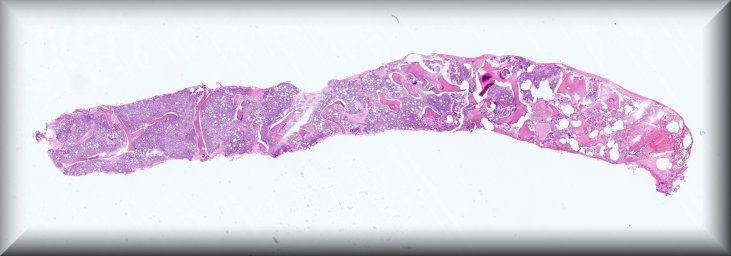

Caso 4.- Paula Tenhaeff Lackschewitz, Gerónimo Llopis, Raquel Martínez Marcos, Esther Roselló Sastre.

Hospital General Universitario de Valencia.

Varón de 28 años, con antecedente de infección por VIH diagnosticada en 2019 y abandonodel tratamiento antirretroviral. Consulta por un mes de evolución de lesiones cutáneas pápulo-nodulares eritematosas y descamativas, tos seca, pérdida ponderal de 10 kg y edemas enextremidades inferiores. En la exploración presenta fiebre de 39 °C, taquicardia y hepatoesplenomegalia. La analítica muestra pancitopenia severa, hipoalbuminemia,hipertransaminasemia y ferritina >90 000 µg/L. Serologías para VHB, VHC, CMV, VEB yBartonella negativas, con beta-D-glucano positivo. Con sospecha de leismaniasis/linfoma serealiza biopsia de médula ósea.